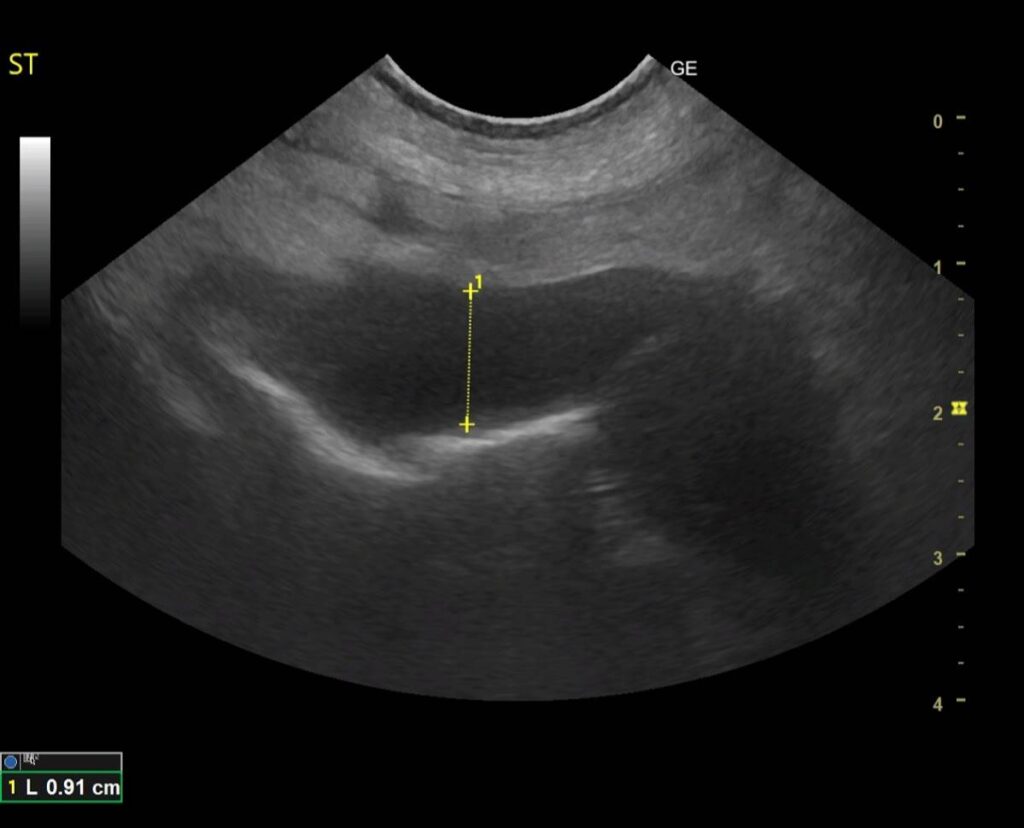

9歳のコーギーが超音波検査で胃壁の肥厚を主訴に来院されました 。

検査をすると胃のリンパ腫が疑われました。 抗がん剤治療で食欲不振と嘔吐は改善しました。